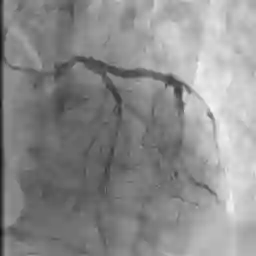

The adoption of machine learning in healthcare calls for model transparency and explainability. In this work, we introduce Signature Activation, a saliency method that generates holistic and class-agnostic explanations for Convolutional Neural Network (CNN) outputs. Our method exploits the fact that certain kinds of medical images, such as angiograms, have clear foreground and background objects. We give theoretical explanation to justify our methods. We show the potential use of our method in clinical settings through evaluating its efficacy for aiding the detection of lesions in coronary angiograms.